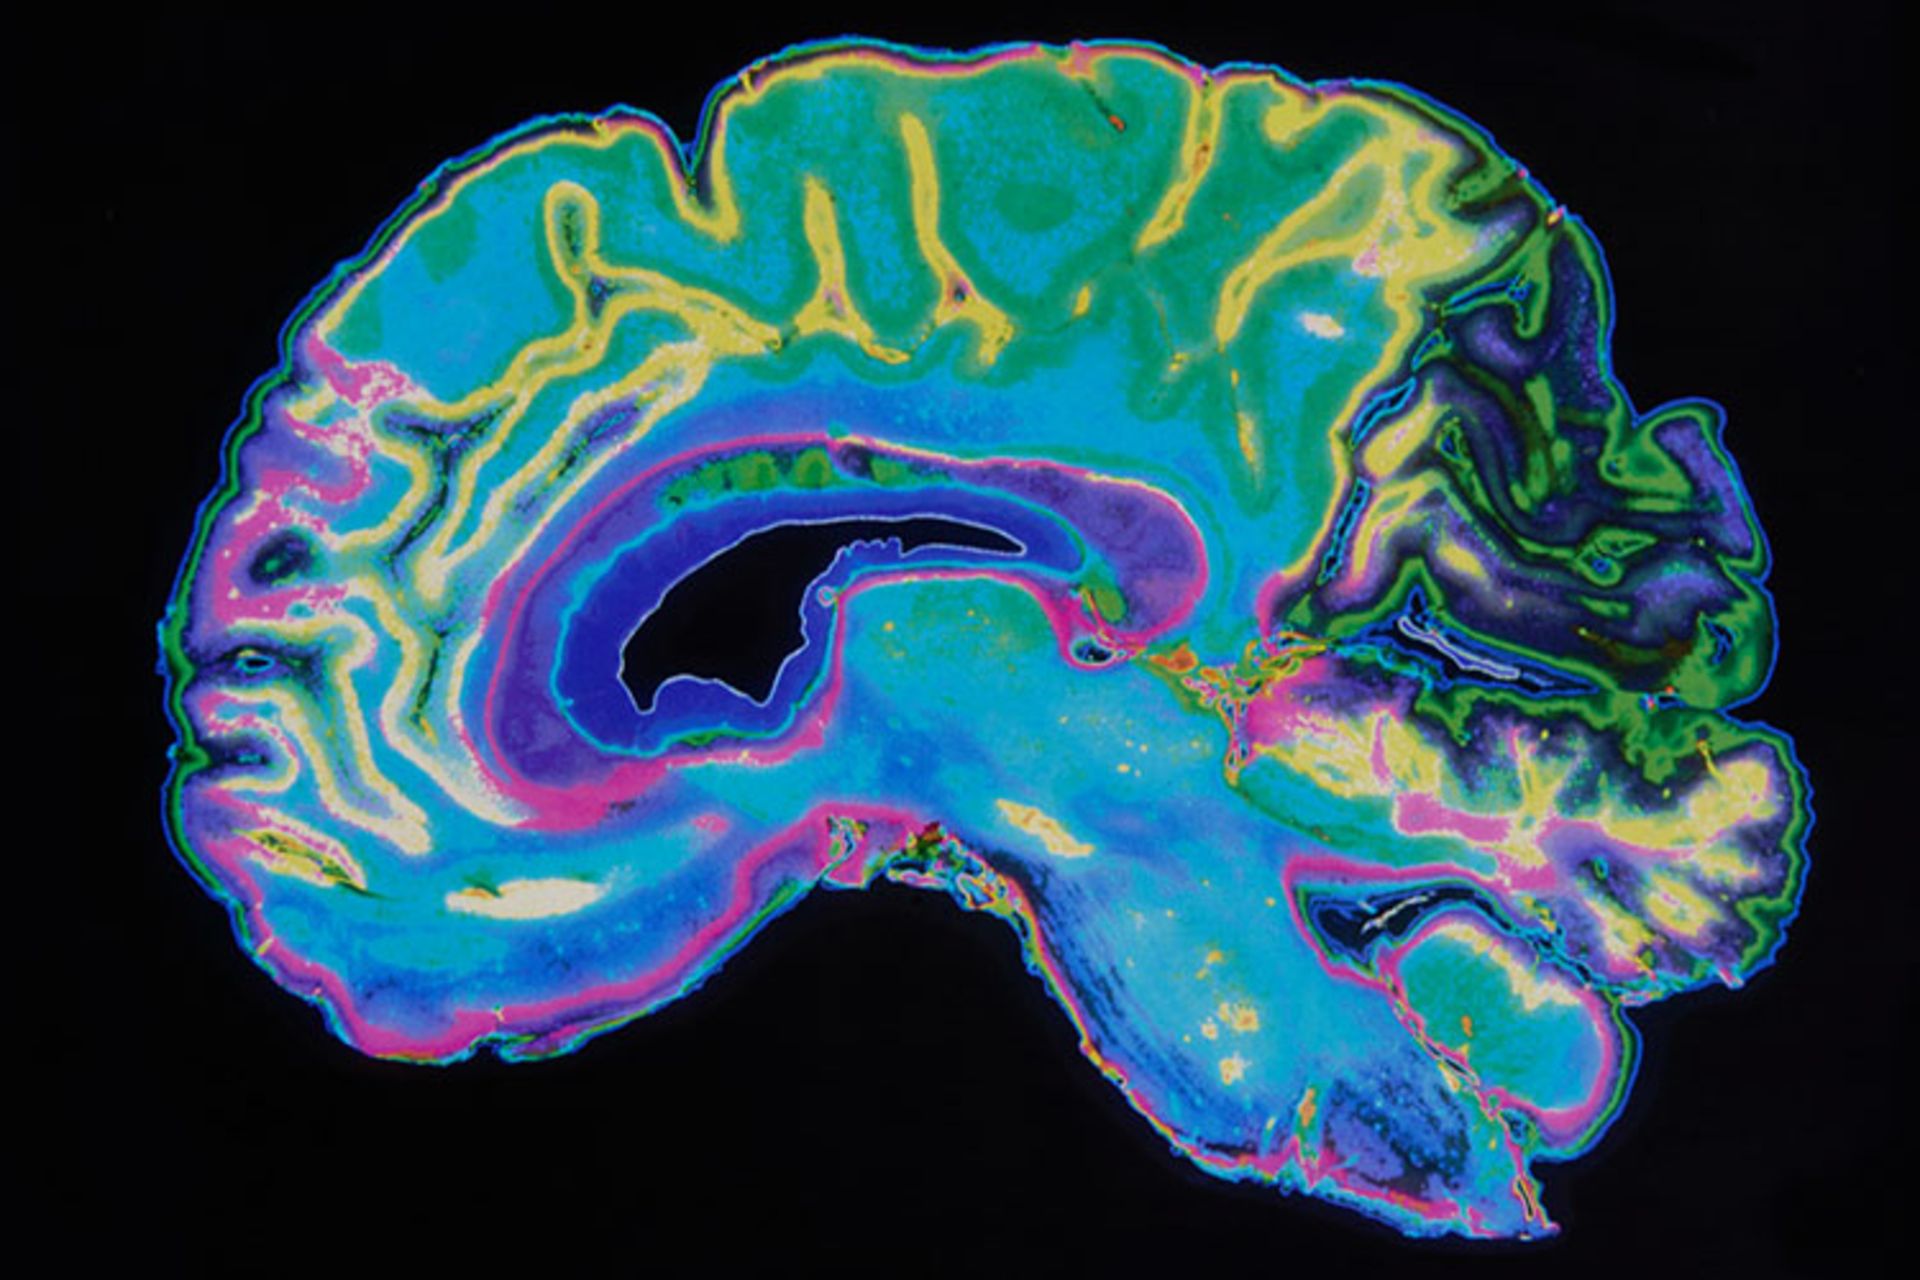

روان‌گسیختگی، اسکیزوفرنی یا شیزوفرنی (Schizophrenia) یکی از بیماری‌های نادر مغزی است که منجر به از کار افتادگی فرایند‌های فکری بیمار می‌شود و قدرت پاسخگویی عاطفی او را ضعیف می‌کند. در حال حاضر، نزدیک به ۳.۲ میلیون نفر از کل جمعیت آمریکا، از این بیماری رنج می‌برند؛ این بیماری نادر می‌تواند زندگی هر شخصی را فلج کند. به‌زودی، فناوری هوش مصنوعی شرکت IBM در کنار تحقیقات دانشگاه آلبرتای کانادا به پزشکان کمک می‌کند که علائم شروع و شدت این بیماری را با یک آزمایش ام‌آرآی و بررسی جریان خون مغر توسط یک شبکه‌ی عصبی ساخته‌شده، تشخیص دهند.

گروه تحقیق، در ابتدا این شبکه‌ی عصبی را روی تصاویر fMRI اسکن شده از مغز ۹۵ نفر امتحان کرد؛ تعدادی از این ۹۵ نفر از بیماری اسکیزوفرنی رنج می‌برده‌اند و بقیه سالم بودند. این تصاویر، وضعیت جریان خون را در قسمت‌های مختلف مغز، هنگام انجام ورزش‌های ساده‌ی صوتی نشان می‌دهد. شبکه‌ی عصبی ساخته‌شده توانست بیماران مبتلا به اسکیزوفرنی را با دقت ۷۴ درصد مشخص کند.